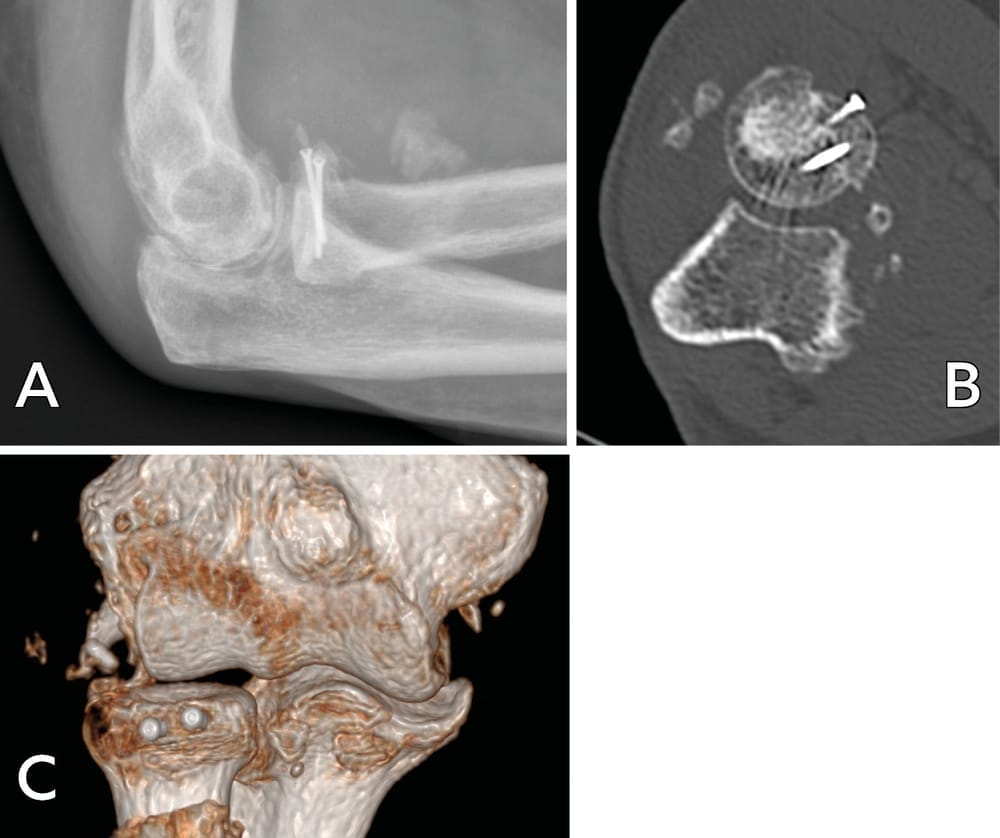

Ablation of the hardware between 12 and 18 months later. Radiological assessment shows consolidation and integration of the graft (Figure 5).

At the most recent follow-up after 2 years, the ranges of motion in flexion–extension were 0/20/135 on the right and left, with full and symmetrical pronation and supination. However, the Jamar dynamometer assessment showed a deficiency in strength, with 6 kg on the right wrist and 2 kg on the left, related to ulnar neuropathy, and overall the functional outcome was poor and had led to post-traumatic depression.

There was a circular free fragment involving 25% of radial head surface, but it was insufficiently thick for fixation to be possible. A circular graft was harvested and fixed with three mini screws, with satisfactory stability (figure 7).

After 3 months, the ranges of motion in flexion–extension were 0/0/130, pronation–supination was 0/20/135 and wrist strength on the Jamar dynamometer was 20 kg, compared to 30 kg on the left side.